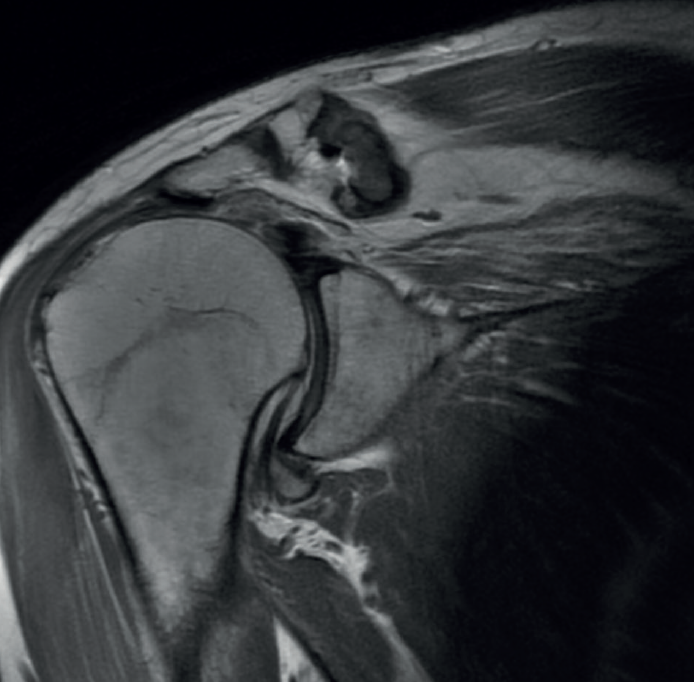

The preoperative evaluation must take a number of aspects into account, including patient age, pain, disability, functional demands and the patient expectations. In this respect, the patient must be duly informed about the expectable functional results. We also must consider other factors that can affect the surgical outcomes, such as patient comorbidities, deltoid muscle and subscapularis function, the integrity of the coracoacromial arch, the presence of arthrotic changes (Figure 1), and the need for the patient to enter prolonged rehabilitation. The main symptoms of massive ruptures of the rotator cuff are typically pain, weakness and loss of mobility(13,14). Irreparable massive ruptures are a common cause of intense pain and often prove extremely disabling for the patient. In general, patients with posterosuperior cuff rupture present reduced flexion-elevation and abduction, and total or partial loss of active external rotation(15,16). A positive external-rotation lag sign and positive hornblower sign are indicative of a deficit of the posterior cuff with the disabling of external rotation, and are associated with irreparable rupture of the teres minor and advanced fatty infiltration(17,18). The appearance of these signs at exploration is associated with poor outcomes of transfer of the latissimus dorsi(13,19). Weakness proves highly variable, and in extreme degrees we observe pseudo-paralysis. Although consensus is lacking, pseudo-paralysis in elevation could be defined as the inability to perform active flexion-elevation of 90º in the absence of nerve damage and with preserved passive mobility. External rotation pseudo-paralysis is defined as the complete loss of active external rotation strength in the presence of unrestricted passive external rotation and the absence of neurological lesions. Some authors consider pseudo-paralysis to be a contraindication to transfer of the latissimus dorsi(20), and is seen to be associated with poor outcomes, since it does not afford the necessary strength to overcome a pseudo-paralytic shoulder and achieve postsurgical elevation(12). Most authors agree that the deltoid muscle must be in good condition in order to perform transfer(21). Irreparable rupture of the subscapularis is an absolute contraindication to this kind of transfer, due to anterior escape of the humeral head when the deltoid muscle contracts in the absence of the subscapularis(9). However, good results can be obtained in partial ruptures of the upper third of the subscapularis that can repaired in the same surgical step(21)(Figures 2 and 3).